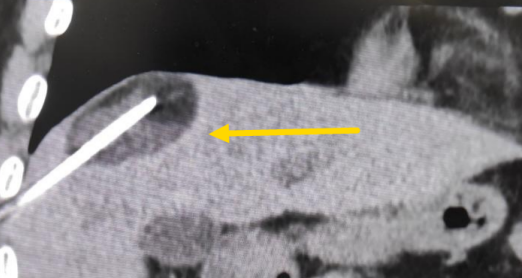

這個(gè)患者病變位置刁鉆,穿刺難度大,冷凍消融的難點(diǎn)在于既要不損傷膈肌和肺組織,同時(shí)又要盡最大可能完全消融腫瘤。術(shù)前陳寶瑩主任、李鐵柱教授、兀云飛醫(yī)生詳細(xì)設(shè)計(jì)進(jìn)針路徑、布針計(jì)劃,術(shù)中微創(chuàng)團(tuán)隊(duì)協(xié)調(diào)配合,李鐵柱教授仔細(xì)操作,精準(zhǔn)到位,順利完成兩個(gè)病變的布針,遂啟動(dòng)治療,先快速降溫到-150多度,再升溫至15?,經(jīng)過兩個(gè)循環(huán)反復(fù),即刻觀察到病變完全被冰球覆蓋,同時(shí)周圍臟器無損傷,術(shù)中患者幾乎沒有疼痛,還和醫(yī)生聊起了天。

術(shù)中冰球形成